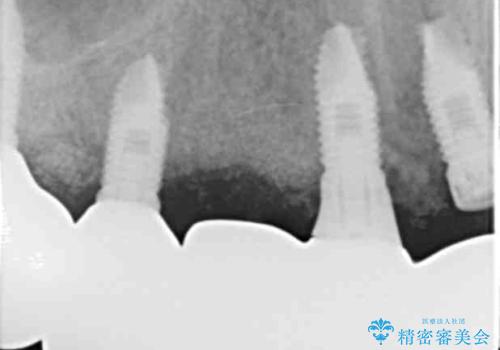

長期的予後不良と判断した右上3フィクスチャーを除去し、人工骨による骨増生及び右上2に埋入を行いました。

保存可能な右上1のフィクスチャーは粘膜下にスリープさせ、左上2の埋入を行いました。

当初は上顎③2①12③ブリッジの予定でしたが、リカバリー手術後上顎3②11②③ブリッジによる補綴を行いました。